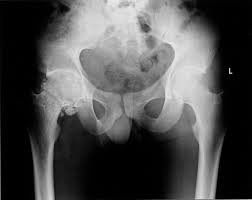

بالنسبه للـ PHYSICAL EXAMINATION او الفحص :

بالنسبه للـ Tenderness اذا كانت الحاله external يكون

حول الـ lateral ITB والـ gluteusmaximus

اما اذا كانت internal يكون التندرنس حول الـ femoral triangle